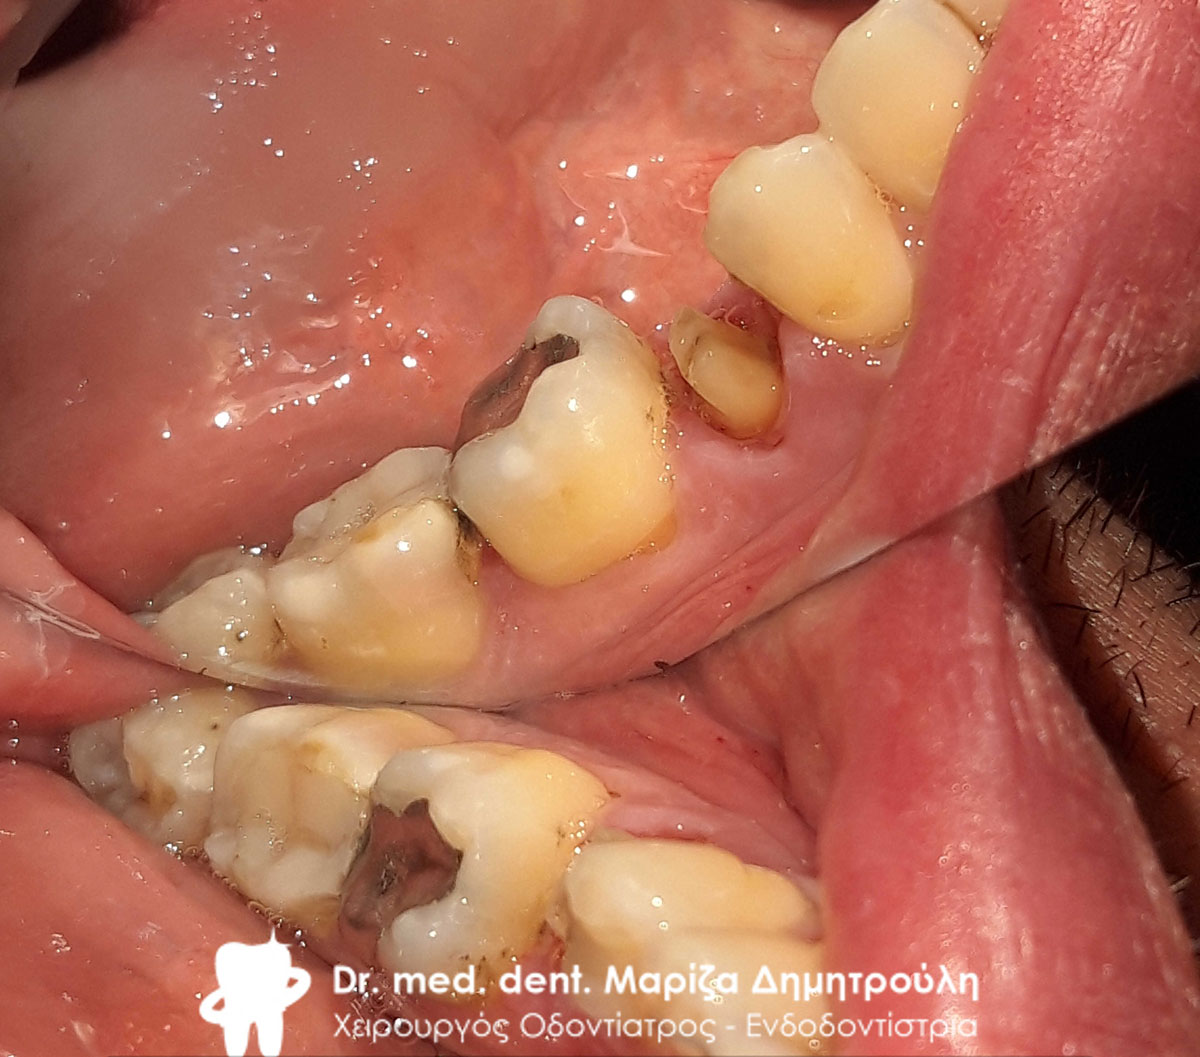

Περιστατικό – Ολοκεραμική στεφάνη / θήκη ζιρκονίου στην αριστερή πλευρά της κάτω γνάθου

Ο ασθενής είχε ένα παλιό μεγάλο σπασμένο σφράγισμα στον κάτω γομφίο. Το δόντι αρχικά απονευρώθηκε και στη συνέχεια καλύφθηκε με ολοκεραμική θήκη ζιρκονίου.

Αρχική κλινική εικόνα του δοντιού με το παλιό σπασμένο σφράγισμα

Κλινική εικόνα της ανασύστασης του δοντιού

Τελική εικόνα της ολοκεραμικής θήκης